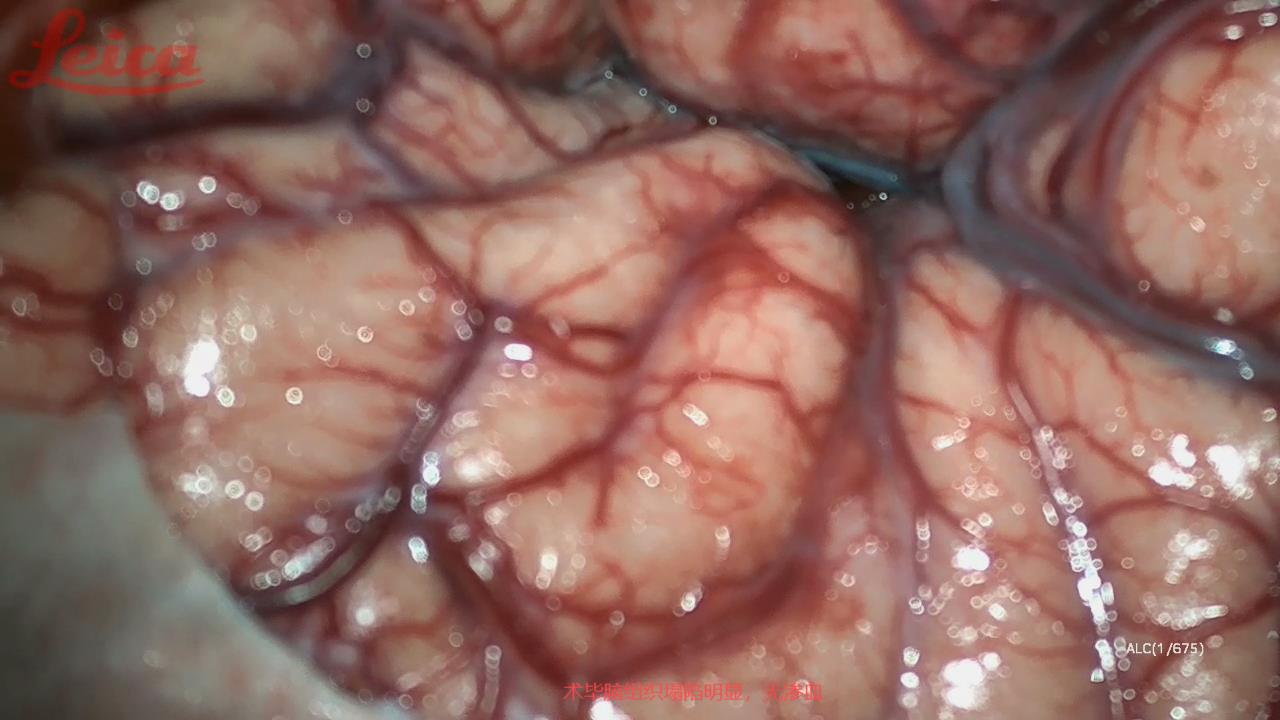

经外侧裂-岛叶造瘘清除血肿简要

经外侧裂-岛叶造瘘清除基底节出血